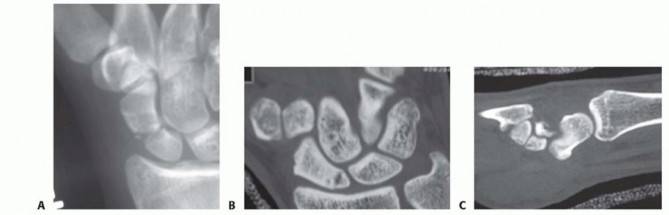

Accurate preoperative assessment is the cornerstone of successful scaphoid reconstruction. Standard posteroanterior (PA), lateral, scaphoid view (PA with ulnar deviation), and semi-pronated oblique radiographs are mandatory. However, plain radiography often underestimates the degree of comminution, bone loss, and angular deformity.

Computed Tomography (CT) is the gold standard for evaluating scaphoid nonunions, assessing the extent of osteolysis, and quantifying the humpback deformity. Because the scaphoid lies obliquely within the carpus (flexed approximately 45 degrees to the longitudinal axis of the radius), standard orthogonal CT planes of the wrist do not provide true anatomical cross-sections of the scaphoid.

To accurately assess the intrascaphoid angle and plan for structural grafting, CT images must be reformatted along the true longitudinal and short axes of the scaphoid.

Images obtained in this specialized sagittal plane are optimal for measuring the intrascaphoid angle and quantifying the degree of volar flexion (humpback deformity) of the distal pole relative to the proximal pole.

Interpretation of images obtained in this true coronal plane is straightforward, allowing for precise evaluation of the fracture gap, cyst formation, and the integrity of the proximal pole articular surface.